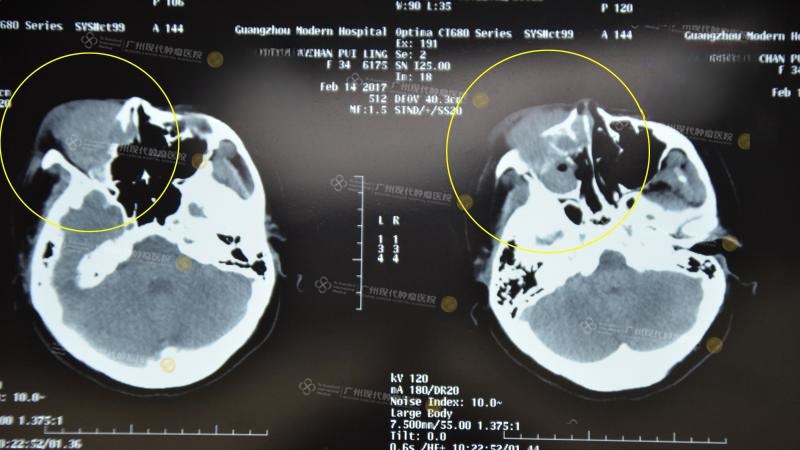

Trước khi điều trị tháng 2 năm 2017

Khoang mũi chứa đầy dịch từ khối u, nhãn cầu bị đè lên và di chuyển

Tháng 3/2017, lần đâu tiên điều trị can thiệp

Dịch ở khoang mũi giảm hẳn, cơ bản đã trở về bình thường, nhãn cầu hồi phục

Trước khi đi điều trị và sau lần can thiệp đầu tiên